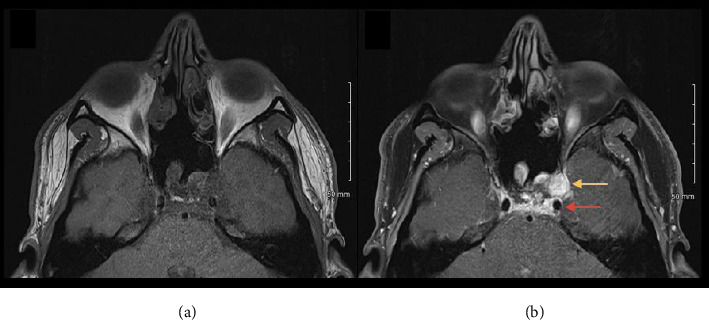

在某些情况下,年轻健康的心脏功能强大且有血管迷走神经性晕厥病史的患者发生心脏骤停的风险增加。迷走神经张力的增加导致动脉压的正常维持转变为副交感神经激活和交感神经抑制,放大传入机械感受器,并在极少数情况下引起心跳停止。我们报告一例17岁的晕厥病史患者,在内镜下鼻内切除骨内黏液瘤后,在麻醉后护理病房(PACU)恢复时,在保持意识和保护气道的情况下进入心跳停止。开始胸外按压并给予肾上腺素,使患者迅速恢复自然循环。在转至重症监护室时,患者采用Fowler位,心率降至20bpm,引起血管迷走神经性晕厥,随后患者仰卧并给予0.8 mg甘罗酸钠治疗。本例中交感神经对副交感神经张力的改变导致心跳停止,以及肾上腺素注射引起的心脏β激动剂刺激提供了Bezold-Jarisch反射发生的证据。该病例提示颅内颈内动脉可能表现出与颈动脉窦相似的机械敏感性,并质疑该反射期间心电图读数的有效性,因为患者在心脏停止时仍保持意识。

In certain contexts, young and healthy patients with a strong heart and a history of vasovagal syncope are at increased risk of cardiac arrest. An increase in vagal tone results in the normal maintenance of arterial pressure shifting into parasympathetic activation and sympathetic suppression, amplifying afferent mechanoreceptors and, in rare instances, inducing asystole. We report the case of a 17-year-old patient with a past medical history of syncope who went into asystole while maintaining consciousness and protecting his airway when recovering from anesthesia in the postanesthesia care unit (PACU) following endoscopic endonasal resection of an intraosseous clival myxoma. Chest compressions were initiated and epinephrine was administered, allowing for return of spontaneous circulation to be quickly achieved. While being transferred to the intensive care unit, the patient's heart rate dropped to 20 bpm while sitting in Fowler's position, causing vasovagal syncope which was then resolved by laying the patient supine and 0.8 mg of glycopyrrolate administration. The altered sympathetic to parasympathetic tone resulting in asystole within this case and cardiac beta-agonist stimulation by epinephrine injection provide evidence that the Bezold-Jarisch reflex occurred. This case suggests that the intracranial internal carotid arteries can potentially display similar mechanical sensitivity as the carotid sinus and questions the validity of electrocardiogram readings during this reflex, as the patient remained conscious while in asystole.